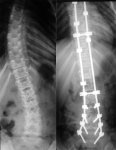

Посоны, по сколиозу кто-нибудь косил? Можете запостить точные формулировки своих диагнозов?

Мимо вторая степень, 13 градусов в грудном, 10 в пояснично-крестцовом.

Мимо вторая степень, 13 градусов в грудном, 10 в пояснично-крестцовом.

Скосил по сколиозу, 11 и 10 градусов, все заебок, пиздуй смело... Было 2 года назад.

Можешь доставить документы? Там про ротацию и фиксированность/нефиксированность что-либо сказано? Снимки лёжа или стоя делал?

спондилограммы грудного и поясничного отделов выполненных стоя и лежа

боковая деформация позвонка

искривление грудного отдела стоя 14 град лежа 13 град с ротацией тел позвонков против ч.с.

заключение собственно - боковая деформация тела позвонка, левосторонний фиксированный сколиоз грудного отдела позвоночника второй степени.

тут есть некая тонкость, фиксированный сколиоз определяется по цифрам, но могут потребовать и явно указанных ротаций-деформаций, так как в списке болезней сколиоз определяется двояко, что в принципе дает возможность обжалования (которое обычно может вывести из-под текущего призыва чисто по времени рассмотрения).

Алсо лично меня отправили заверять (лично) это у врачей главного военкомата, они посмотрели рентгенограммы, сказали ну это не второй степени хотели меня уже в армию отправить, но я завыл завизжал так, знаешь, не знаю, что нашло на меня ну а они такие хуй с ним просто ну хуй с ним но военник дали, думаю просто постращать-повыёбываться это отпустили.

пикрелейтед, но не мой.

>фиксированный сколиоз определяется по цифрам

Так всё-таки что они понимают под фиксированным? Ни один врач не знает, что это за хуйня такая.

фиксированность - белеберда, но они могут пытаться трактовать в свою сторону http://prizivnikov.net/niv-info.html

в рб четко указанно (сколиоз II степени), если что обжалуй в обл вк, на крайний случай в суд

это значит, что лежа твой сколиоз второй степени не становится степени первой, т.е. меньше 11 градусов. врачи не знают, так как это явно чисто солдафонская выдумка.

То есть с любым сколиозом второй степени с ротацией писать жалобу про то, что никакой фиксированный сколиоз в РБ не упомянут?

То есть на самом деле откосить можно, если в стоячем положении вторая степень, в лежачем искривление не исчезает полностью, и в стоячем есть ротация, а в случае разговоров про фиксированный сколиоз следует мешать их с говном?

кстати, сколиоз случайно не S образный

я бы на твоем месте, сначала отправил заказным письмом в военкомат заявление с перечнем заболеваний (сколиоз), статьей и приложенным описанием рентгена (образцы есть на форумах)

и если признают годным, то обжалуеш в областной военкомат, про фиксированность и тп я бы не стал писать,

ведь статье говорится >сколиоз II степени

К пункту «в» относятся: фиксированные приобретенные искривления позвоночника, сопровождающиеся ротацией позвонков (сколиоз II степени, остеохондропатический кифоз с клиновидной деформацией 3 и более позвонков со снижением высоты передней поверхности тела позвонка в 2 и более раза и др.);

>сколиоз случайно не S образный

S-образный. Ротация, судя по пикчам, есть в обеих дугах. Завтра попытаюсь заставить ортопеда написать про неё в карте.

А есть ли смысл письменно отказываться от снимков лёжа, если на руках бумажки с диагнозом "сколиоз II степени"?

S-образные искривления позвоночника во фронтальной плоскости (в положении стоя) всегда фиксированные и относятся к структурным изменениям. Источник: «Травматология и ортопедия», том 4, авторы статьи — М.Г. Дудин, С.Ф. Леснова. Редакторы тома: чл.-корр РАМН, засл. деят. науки РФ профессор Н.В. Корнилов и профессор Э.Г. Грязнухин, Спб, изд. «Гиппократ», 2006.

я копировал этот кусочек в письмо, когда отсылал в вк заявление ) но всё равно фиксированность это придуманное врачами военкомата и просто стоя 11 достаточно для освобождения

>в лежачем искривление не исчезает полностью,

оно не может полностью исчезнуть

если ты не из резины

>ротация

она либо есть, либо нет, ибо устойчивая деформация, являющаяся чуть ли не главным критерием сколиоза

>а в случае разговоров про фиксированный сколиоз

я думаю, тут зависит от конкретного военкомата. мне повезло, так как все что нужно у меня было.

а всякие тонкости и переходные случаи - это уже отдельно надо смотреть

вообще говоря пункт "в" ст.66:

" фиксированные приобретенные искривления позвоночника, сопровождающиеся ротацией позвонков", все. т.е. по идее, если есть искривление и ротация - должно быть достаточно. Но фактически, может сидеть старичок, придирчиво намеряет на твоем "лежа" 10.49999 градусов и радостно прокряхтит "годен". тут уже можно пытаться обжаловать. и подкручивать плоскогубцами позвонки